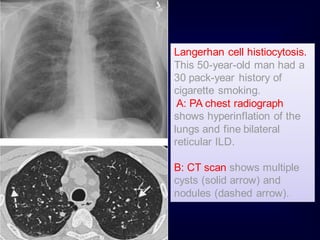

Langerhan cell histiocytosis.

This 50-year-old man had a

30 pack-year history of

cigarette smoking.

A: PA chest radiograph

shows hyperinflation of the

lungs and fine bilateral

reticular ILD.

B: CT scan shows multiple

cysts (solid arrow) and

nodules (dashed arrow).

Langerhan cell histiocytosis. This50-year-old man had a 30 pack-year history of cigarette smoking. A: PA chest radiograph shows hyperinflation of the lungs and fine bilateral reticular ILD. B: CT scan shows multiple cysts (solid arrow) and nodules (dashed arrow).